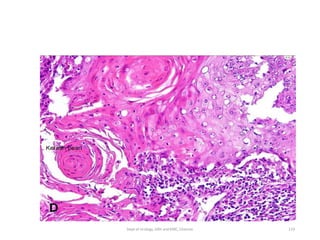

• Muscle invasive

• Histology:

• Invading urothelium shows irregular nests, single cell

infiltration or tentacular finger-like projections

• Stromal response

-desmoplasia,

-retraction or

-inflammation.

• Assess level of invasion for staging

.

• Presence and status of involvement of muscularis propria

should be reported in TURBT specimen for adequate staging.